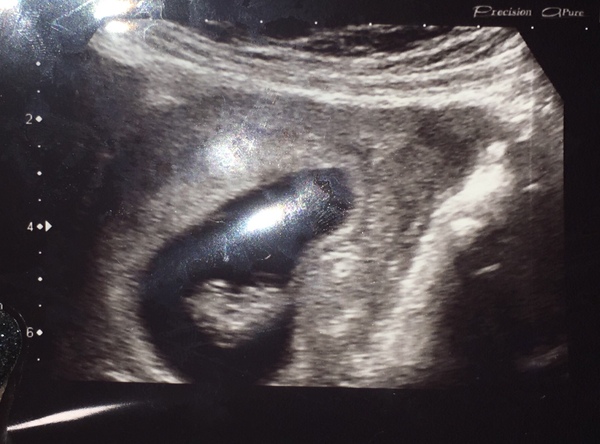

BoomKapow · 18/09/2018 18:45

Just had my scan. All looking good and I’m now further than I was when I miscaried. Dates match mine exactly so 8 weeks today. It was internal cause I have a retroverted uterus (which I knew about already).